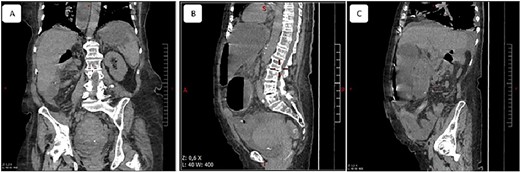

A 65-year-old woman presented to the emergency department with a complaint of acute abdominal pain and distention accompanied by nausea, vomiting and constipation of 2 days. She had a history of diabetes, hypothyroidism, dyslipidemia, mixed connective tissue disease and cholecystectomy. On examination, she had signs of septic shock with a hemodynamic instability, a Glasgow coma scale of 13 with generalized abdominal defense. Initial blood count showed elevated white blood cells (WBC) 22 000 elem/mm3 and C-reactive protein (CRP) of 500 mg/l and procalcitonin of 96 ng/ml. Her lactate on venous blood gas sampling doubled within an hour from 1.64 to 2.3 mmol/l. An urgent abdominal computed tomography (CT) was performed and revealed a dilated loop of bowel within the left upper quadrant and the lesser sac through the foramen of Winslow (Fig. 1). Furthermore, peritoneal fluid and some air bubbles related to intestinal perforation were observed in the omental bursa (Fig. 2). There was also mass effect on the hepatic hilum anteriorly and the inferior vena cava posteriorly. The stomach was pushed back antero-laterally with stretched mesenteric vessels directed to a central point (Fig. 3).

(a) Coronal view of computed tomography of abdomen and pelvis shows the dilated cecal pole and the stomach displaced anteriorly. Peritoneal fluid and some air bubbles related to intestinal perforation were observed in the lesser sac can also be observed (arrow head). (b) Closed-loop small bowel obstruction. CT scan shows a radial array of distented small bowel loops (asterisk) with stretched and thickened mesenteric vessels converging to a central point and anterior to inferior vena cava, which is compressed (white arrow).